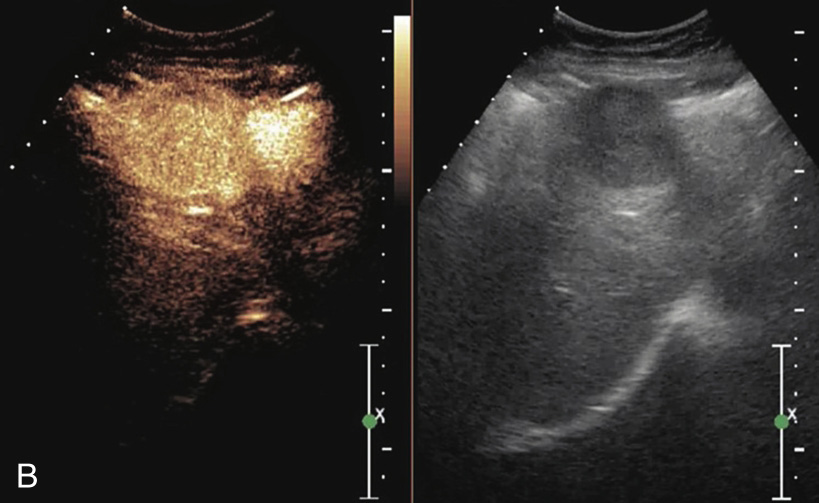

图1-7-1 肝细胞癌灰阶超声图像

病灶呈低回声,内回声不均匀,向肝被膜外凸出